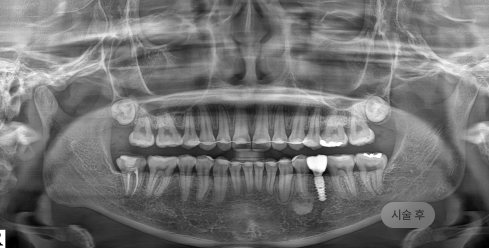

화면을 드래그하여 전/후를 비교해 보세요